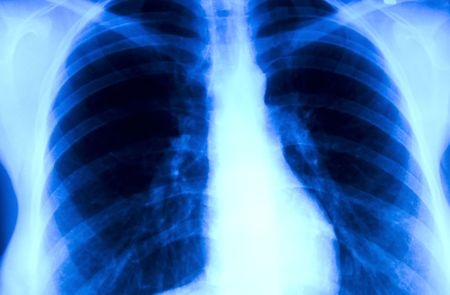

Zgodnie z wynikami badania opublikowanego w Lancet Oncology, pacjenci z wysokim ryzykiem rozwoju raka płuca, z prawidłowym (ujemnym) wynikiem corocznego niskodawkowego badania tomografii komputerowej (TK) płuc wykazują mniejszą zachorowalność oraz mniejsze ryzyko zgonu z powodu tego nowotworu w porównaniu z całą grupą chorych o zwiększonym ryzyku rozwoju nowotworu, poddanych badaniom przesiewowym.

Na podstawie uzyskanych wyników badacze z Duke University Medical Center w Durham, North Carolina, postawili hipotezę, że być może ta grupa chorych wymaga wydłużenia czasu pomiędzy kolejnymi badaniami przesiewowymi. W ich opinii dane te nie tylko poddają w wątpliwość koniczność corocznego wykonywania badania po uzyskaniu ujemnego wyniku, ale także sugerują, że coroczne badania przesiewowe po kolejnych ujemnych niskodawkowych TK mogą nie być konieczne, a wybór jednego roku jako przedziału czasowego pomiędzy kolejnymi badaniami nie ma podstaw biologicznych. W artykule podkreślono, że pomimo zaleceń amerykańskiej Preventive Services Task Force, aby u osób w wieku pomiędzy 55 a 80 lat wykonywać co roku badanie przesiewowe przy użyciu TK, pracownicy opieki medycznej powinni uwzględnić możliwość niekorzystnych następstw psychologicznych i społecznych, następstwa długotrwałej kumulacji ekspozycji na promieniowanie jonizujące, a także koszty badania przesiewowego, wykonywanego co roku przez 25 lat. Zdanie dotyczące badań przesiewowych w kierunku raka płuca są ciągle podzielone, a jedynie Stany Zjednoczone zdecydowały się kontynuować ten program, w związku z czym ciągle jest możliwość zastanowienia, kto rzeczywiście wymaga corocznych badań przesiewowych, a u których pacjentów badania można wykonywać rzadziej. Patz i wsp. analizowali dane z National Lung Screening Trial, w którym porównano trzy, wykonywane co roku badania TK z trzema, corocznymi zdjęciami radiograficznymi, wykonywanymi w celu wykrycia raka płuca u osób z wysokim ryzykiem. Uczestnicy badania (n=26231) byli w wieku od 55 do 74 lat, wypalali wcześniej co najmniej 30 paczkolat lub rzucili palenie w okresie ostatnich 15 lat. Z tej grupy u 19066 uczestników badania początkowe badanie TK było ujemne. U tych osób wykazano statystycznie istotnie mniejszą częstość występowania raka płuca w porównaniu z całą populacją 26231 osób (371,88 vs 661,23 na 100000 osób na rok). Ponadto osoby z ujemnym wynikiem badania miały także mniejsze prawdopodobieństwo zgonu z powodu raka płuca, ze współczynnikiem śmiertelności wynoszącym 185,82 w porównaniu z 277,20 na 100000 osób na rok. Raka płuca wykryto u 1,0% wszystkich uczestników badania, u których wykonano początkową TK, natomiast w trakcie drugiego badania nowotwór wykryto jedynie u 0,34% uczestników z ujemnym wynikiem pierwszego badania. W opinii badaczy gdyby nie wykonano drugiego badania, w trakcie całego badania zmarłoby z powodu raka płuca dodatkowo 28 osób w grupie z negatywnym wynikiem TK. Coroczne badanie przesiewowe przy użyciu niskodawkowej TK wykrywa pewną liczbę raków płuca we wcześniejszym stadium, pozwalającym na uzyskanie lepszych wyników leczenia w porównaniu z całkowitym zaniechaniem badań lub corocznym wykonywaniem przesiewowych badań radiograficznych, co może w konsekwencji poprawić wyniki leczenia w określonej grupie chorych. Niemniej jednak badacze podkreślili, że zakres tych korzyści należy ocenić w kontekście ryzyka i kosztów badań, ponieważ zasoby przeznaczone na opiekę medyczną nie są nieograniczone, a społeczeństwo powinno zdecydować w oparciu o dane naukowe w jaki sposób dobrać odpowiednią metodę badań przesiewowych.